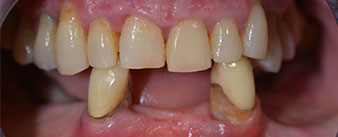

Пациентката е 64-годишна жена с частично обеззъбяване на зъби 38, 33 и 43 и частична долночелюстна протеза (Фиг. 1 и 2).

Необходимото пародонтално лечение и екстракция в челюстта бяха изпълени на по-късен етап, тъй като пациентката е учителка и беше заета с училищни изпити по това време. Тя не можеше нито да се храни, нито да говори нормално, тъй като временната протеза беше много фина и често се чупеше при най-малкия натиск.